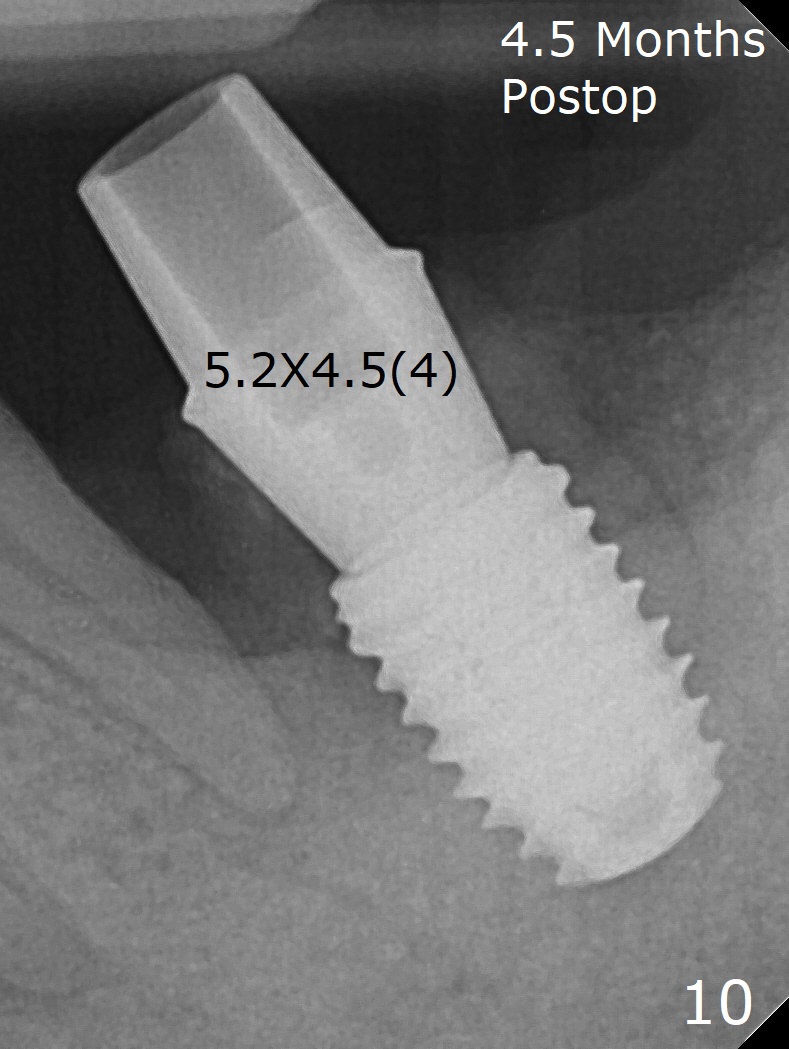

Socket shield (partial extraction therapies) is going to be conducted in this case to form a substitute buccal plate of the 2nd molar (Fig.1 *). The apex of the shield that contacts the 4.5x10 mm dummy implant cannot be removed because of poor access (Fig.2 * (12 mm offset)). Due to high bone density, a 4.5 mm drill has to be used in order to place a 5x7.3 mm definitive implant (Fig.3). In spite of the fact that the implant seems to be completely seated, the implant is ~ 1 mm supracrestal lingually. After implant removal, a 4.5x11.5 mm drill cannot reach the depth due to high bone density. 800 RPM instead of 50 RPM may help. When the implant is reseated, it appears to be .5 mm deeper than before clinically, although it looks incompletely seated in X-ray (Fig.4 <). The insertion torque is 60 Ncm. Allograft mixed with PRF is placed around the implant with cover screw, particularly mesiolinguodistal (Fig.4 *). The sockets of #17 and 18 are approximated with the help of 2 piece of PRF and collagen plug. The wound dehisces 9 days postop (Fig.5,6), although asymptomatic. Forced closure of the sockets with suture seems unnatural. An immediate provisional should have been fabricated. CT shows possible loss of part of bone graft (Fig.7). Regraft seems necessary in the appointment of uncover. Antibiotic is prescribed for another week. The gingiva seems healthy around the exposed healing screw 16 days postop (Fig.8). After debridement, the healing screw is then changed to a 4.5x5 mm healing abutment. The majority of the bone graft is lost without immediate provisional in 4 months (Fig.9 * (<: socket shield)). Then a 5.5x5 mm healing abutment is inserted for impression next appointment. A 5.2x4.5(4) mm cemented abutment is placed before impression (Fig.10). With socket shield (Fig.11 ^), the buccal gingiva looks more keratinized than the lingual one (Fig.12 *). Photos are taken immediately pre-cementation. Socket shield (*) covers the implant and abutment buccally (Fig.13 CT taken immediately pre-cementation).